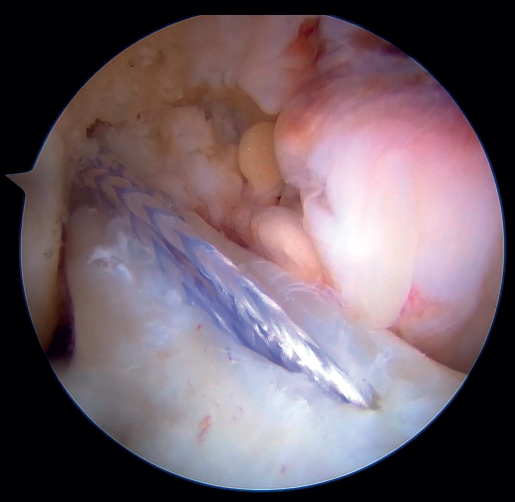

Figura 9. Paso del sistema de fijación cortical tras solidarizarlo a las suturas pasadas por el ligamento cruzado anterior (LCA). Rodilla derecha, visión desde el portal anterolateral.

Figura 10. Resultado final de la reparación directa del ligamento cruzado anterior (LCA) con sistema de fijación cortical e InternalBrace® con cinta de alta resistencia. Rodilla derecha, visión desde el portal anterolateral.